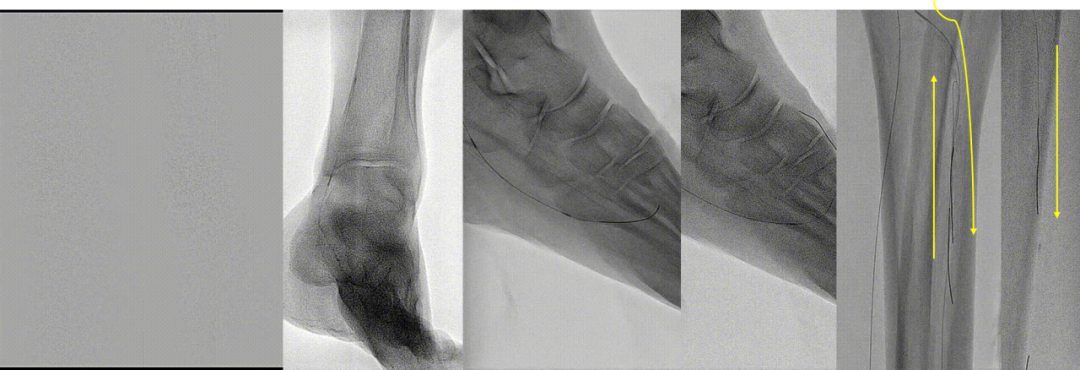

区域化操作策略:

平直区域:可快速通过(真腔或内膜下);

关键区域(如CTO开口、出口、BTA区域):必须谨慎操作,避免穿孔等并发症。

BTK 标准化开通流程

Ante-True Lumen

Fail + short lesion

Fail →Retro puncture

Fail → SAFARI/CART/r-CART

Fail + long lesion

Fail → PA/PTA

Fail → ATA

Fail → PCA

Fail → Puncture

Fail → Pedal arch

Antegrade access with retrograde wireguided